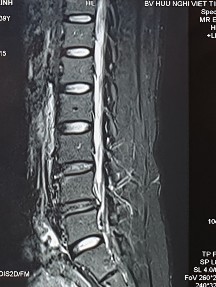

2. Hình ảnh khảo sát dẫn truyền thần kinh, điện cơ đồ và MRI (thực hiện trên mẫu nghiên cứu: bệnh nhân Hoàng Đình H., mã số bệnh nhân 1010320).

Bệnh nhân H., khi khám lâm sàng có biểu hiện tổn thương rễ thần kinh L4, L5, S1. Kết quả xét nghiệm điện cơ thấy: dẫn truyền thần kinh thấy mất phản xạ H, nhưng kết quả khi điện cơ kim có biểu hiện tổn thương rễ thần kinh L5 . Kết quả chụp cộng hưởng từ là tổn thương thoát vị L4 – L5, L5 – S1. Như vậy, trên bệnh nhân này vị trí tổn thương thực tế khi kết hợp phối hợp giữa khám lâm sàng, chẩn đoán hình ảnh và chẩn đoán chức năng là vị trí rễ thần kinh L5.

Hình ảnh thoát vị đĩa đệm trên phim chụp MRI.